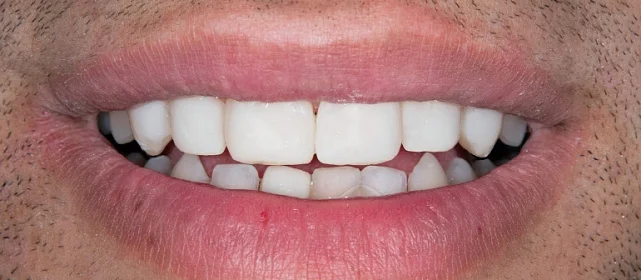

Зубы выровнены, скученность устранена. Установлены несъёмные ретейнеры на обе челюсти, сняты сканы для ретенционных кап. Ортопедия не требуется, рекомендовано лечение у терапевта.

Решение: Установили брекеты на обе челюсти. Расширили дуги, убрали скученность — всё за 15 месяцев. Визиты раз в 4–6 недель для замены дуг. После снятия зафиксировали ретейнеры на обе челюсти, сняли сканы для кап. Ортопед подтвердил, что протезирование не требуется. Терапевт рекомендовал лечение — пациентка записана.

Пятнадцать месяцев!! Я морально готовилась к двум годам минимум, начиталась всякого в интернете. Виктория Юрьевна на первой консультации сказала, что случай не самый сложный и должны уложиться побыстрее. Так и вышло. Из неприятного — первая неделя после установки и пара дней после каждой замены дуги. В остальном нормально, привыкла быстро. Когда сняли и я увидела зубы — не поверила, что это мои. Теперь вот к терапевту надо сходить, подлечить пару зубов, и вообще всё.